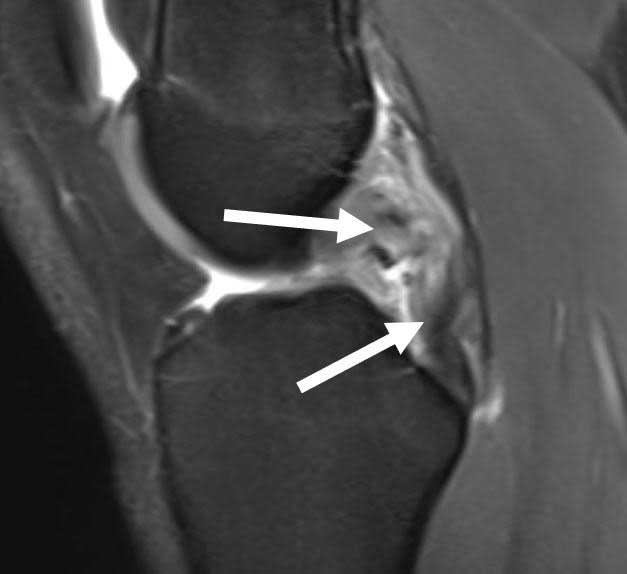

Arthroscopic Meniscal Repair

Arthroscopic Meniscal Debridement